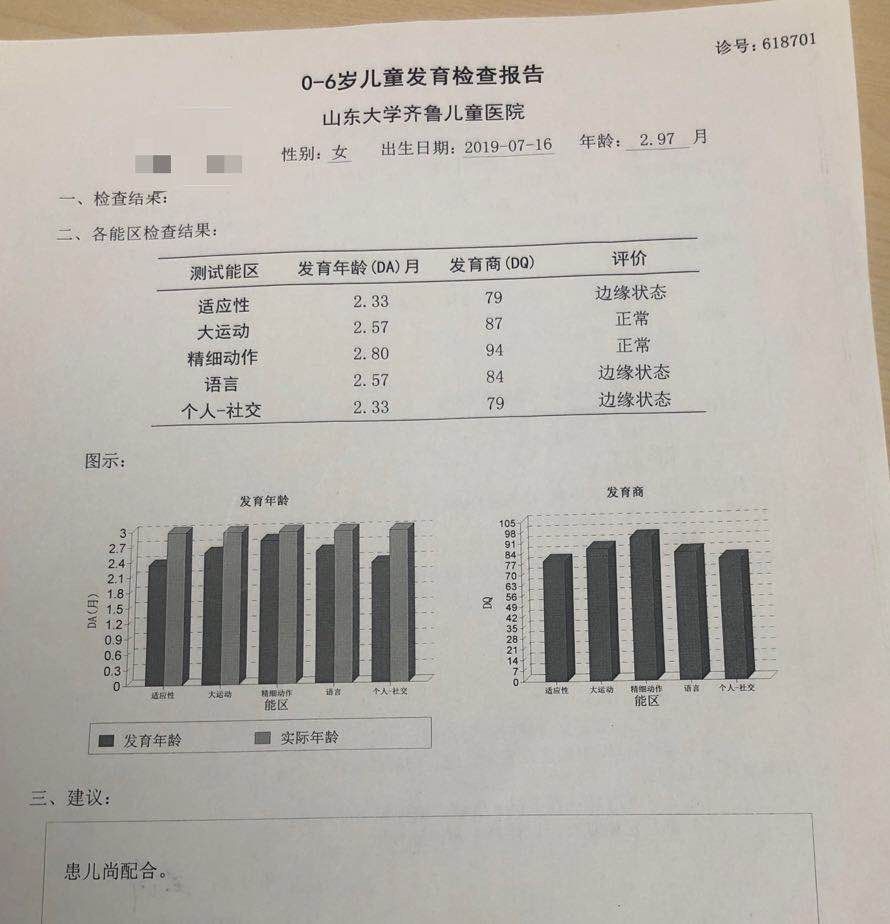

宝宝3月大智力发育监测